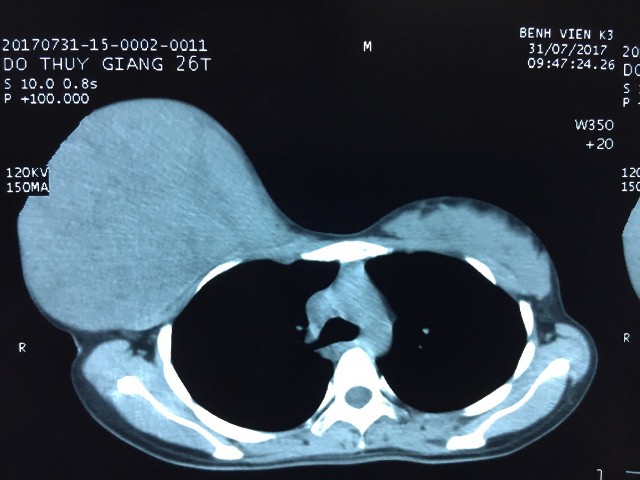

Hình ảnh u tuyến vú rất to, chiếm toàn bộ tuyến vú phải của bệnh nhân G.

Tại đây các bác sĩ khoa Ngoại Vú đã khám sơ bộ và chỉ định làm được làm các xét nghiệm đánh giá toàn trạng, chụp phim đánh giá tổn thương. Qua hình ảnh chụp phim cho thấy, u lớn và chiếm toàn bộ tuyến vú phải của bệnh nhân.